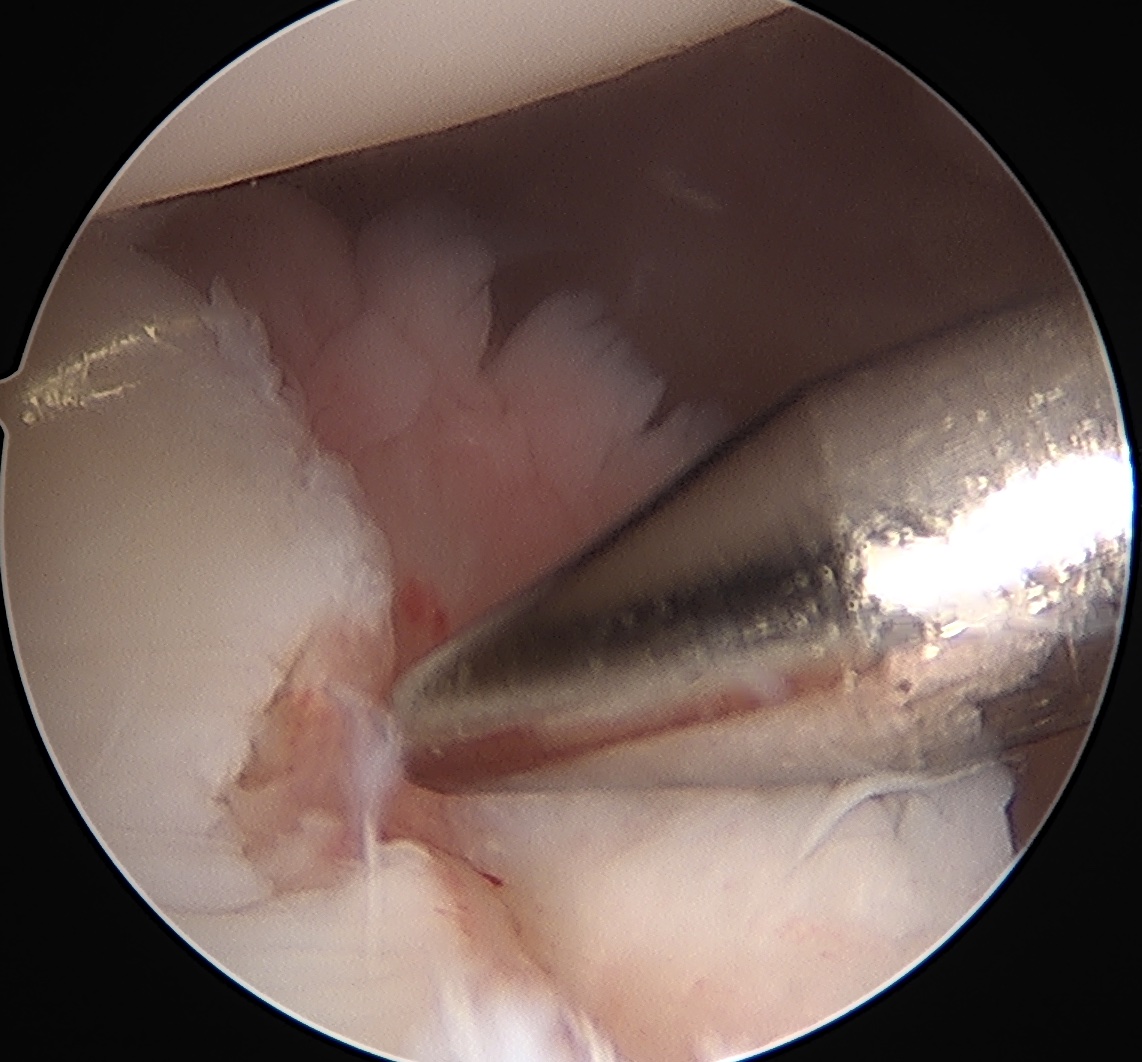

Posterior labral repair

Arthroscopic posterior labral repair / capsular plication

Technique

- posterior labral repair